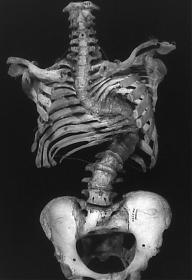

Below is a picture of the skeleton at the Stonehenge site and the one of King Richard III at the car park.You can see the difference in how the spine lays when it is a natural straight spine, even though laying in a hole in a curved position. The vertabrae in King Richard's spine formed together in an unnatural curve.

Below is a picture of the skeleton at the Stonehenge site and the one of King Richard III at the car park.You can see the difference in how the spine lays when it is a natural straight spine, even though laying in a hole in a curved position. The vertebrae in King Richard's spine formed together in an unnatural curve.

I know a little bit about scoliosis from my social worker days, when I has lots of clients who had it, usually people who also had some other problem, like CP. Anyway, the hunchback, fetal skeleton has kyphosis, something we are told that the Richard skeleton expressly did not have.

Second, the Richard skeleton, the way it is laid out, as an anthropological specimen, just doesn't look like anything in nature. No one with scoliosis has a spine that juts out, then becomes straight again, although from pictures I've seen, some people who have had fractured vertebrae, and been lucky enough not to get spinal cord damage, sometime get a funny kink in the spine, that looks like scoliosis at first glance, but isn't. The jut in that skeleton is way too pronounced to be the result of that, either, though.

Anyway, when someone has a wide angle c-curve running the length of the spine, it's one thing, but when someone has an acute angle curve, invariably, the spine then curves also to the other side, so the upper body weight is still evenly distributed, and you get an s-curve. It's also pretty unusual for the curve to end below the neck, so the cervical vertebrae are all straight.

Wow. That first pic is from someone who had a combination of scoliosis, and kyphosis, giving him a corkscrew spine. That must have been awful. If you look at the ribcage, it looks like the lungs couldn't expand very well. At least it looks like a male pelvis. I'll bet a women with that kind of curvature was doomed to mid-term miscarriages. I'll bet that person was in a wheelchair toward the end of life.

The lower ones are s-curves. My point about the curve being only one direction is that people with scoliosis tend to carry themselves so their head is still more or less over their coccyx. A very obtuse curve the length of the spine tends to allow for this, but an acute curve, or even one that is more than 90 degrees, but not much more, usually causes a compensatory curve the other direction, and so you get the s-curve.

I said that not because I was arguing that Richard had no curve, just that the poster who said the curve in the skeleton may have become more pronounced after lying in one position for more than 500 years, and therefore give the impression of Richard being more disabled than he actually was. I don't know how much cartilage, or evidence thereof is preserved, although, I'm guessing "none," and that will make the position of the skeleton the best indicator of the curve, but what Richard was able to do in life is really important as well. If you think about how hard it much have been for that very contorted person in the first pic to take a deep breath, and you think how it probably would have been impossible to stay astride a horse if Richard wasn't able to pull his head over the center of his pelvis.